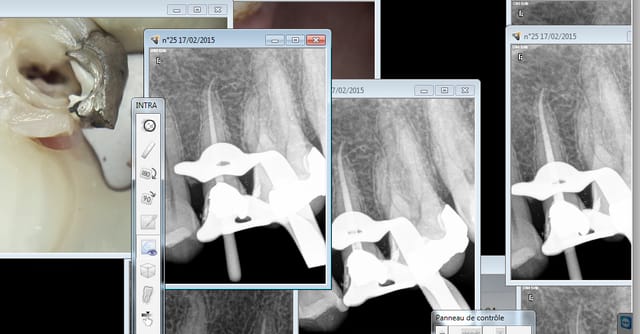

Et une autre spécial MV2. formation gratuite chicot 29. -))))

Moi aussi ca pousse à s'améliorer. Il y a une petite différence par rapport à d'habitude sur cette 25. Laquelle ?

Ok promis, après j'arrete de faire joujou avec mes "contextes" je sens que ca agace ! -))))))

Capture d e cran 2015 02 17 16.18 - Eugenol

t'as mis la digue =)

...pour 48€....